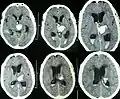

- Troubles cognitifs : la présence de troubles cognitifs spécifiques de l'AAC n'a été soulignée que récemment. Ceci explique un double facteur de confusion qui a pu masquer les troubles cognitifs propres à l'AAC : d'une part, la fréquente association clinique avec la maladie d'Alzheimer, d'autre part, le fait que l'AAC n'a souvent été étudiée que dans le cadre de l'hémorragie cérébrale, souvent responsable de troubles cognitifs potentiellement sévères par elle-même[11]. Néanmoins, il a été montré dans l'étude autoptique déjà mentionnée plus haut que la présence de lésions histologiques d'AAC est associée à un sur-risque de déclin cognitif indépendamment des autres lésions, en particulier celles de maladie Alzheimer[1]. Les études in vivo rendent plus difficile le contrôle de la part des troubles attribuables à la maladie d'Alzheimer. Une étude chez des patients ayant présenté une hémorragie cérébrale montrait un taux plus élevé de démence à un an chez les patients avec une hémorragie lobaire et de l'hémosidérose corticale et des microsaignements (trois signes clés à l'IRM du diagnostic d'AAC)[12]. Le profil cognitif propre à l'AAC est difficile à déterminer. Comparés à des patients souffrant de maladie d'Alzheimer, les patients avec une AAC (sans antécédent hémorragique) avaient des performances significativement meilleures sur les scores de mémoire épisodique mais comparables pour ceux des fonctions exécutives et de vitesse de traitement[13].

- Marqueurs en IRM cérébrale. Outre les marqueurs hémorragiques déjà mentionnés, la valeur diagnostique de quasi tous les marqueurs classiques de microangiopathie à l'IRM ont été étudiés, en particulier pour différencier l'AAC de l'angiopathie hypertensive. En particulier, plusieurs travaux se sont intéressés à la distribution des hypersignaux de la substance blanche. L'AAC semble se caractériser par une tendance à présenter des hypersignaux de substance blanche plutôt cortico-sous-corticale (proche du cortex) alors que l'angiopathie hypertensive touche plus spécifiquement les capsules externes et le tronc cérébral[18]. La présence d'hypersignaux punctiformes en IRM de diffusion a également été considéré comme un marqueur potentiel de l'AAC, mais cette association n'a pas été retrouvée dans une méta-analyse de 2018[19]. À l'heure actuelle, seule la présence de dilatation des espaces de Virchow-Robin de topographie sous-corticale a montré une bonne corrélation avec les données histologiques.